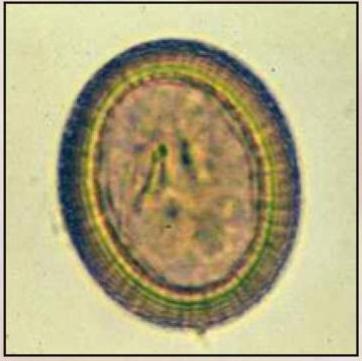

Apacor Odczynniki do analiz parazytologicznych

Odczynniki do analiz parazytologicznych